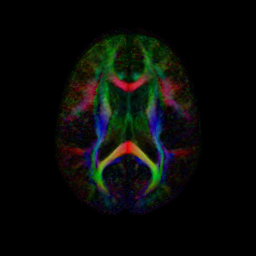

We have begun to apply the DTI atlas building procedure to data provided by the PNL. A combined set of DTI scans from control and Schizophrenic subjects were aligned using the procedure described above. In the atlas space the SZ and CNTL groups are processed to produce voxel-wise statistics for each group. The figure below shows colored FA and mean diffusivity slices for both the CNTL and SZ group. Preliminary work is now being done on region of interest (ROI) hypothesis testing between the two populations.